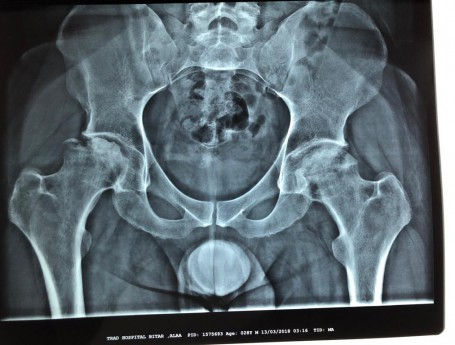

Bilateral Total Hip Arthroplasty Anterior Approach

Total Hip Arthroplasty Anterior Approach